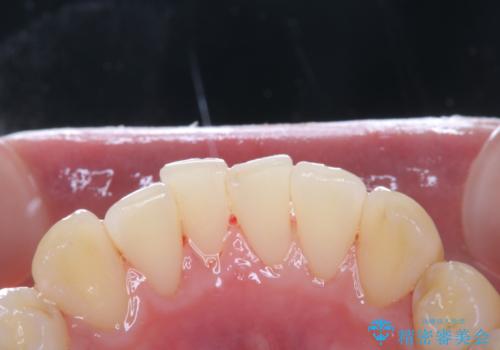

PMTCを行う際には担当の歯科衛生士が、患者様1人1人の虫歯・歯周病などのリスク・ブラッシングスキルなどを確認します。

単なる磨き方の指導だけではなく、歯並びや歯肉の状態、ライフスタイルなどにより、患者様に適した歯ブラシや歯磨剤の選択をしたり、お口のお悩みについてのご相談も承っております。

日々の磨き残しや唾液の成分などによりバイオフィルムや歯石はどうしても付着してしまいます。歯石や汚れを放置していると、そこで病原菌が繁殖す始めます。歯肉に炎症が生じると歯周病などの引き金となります。